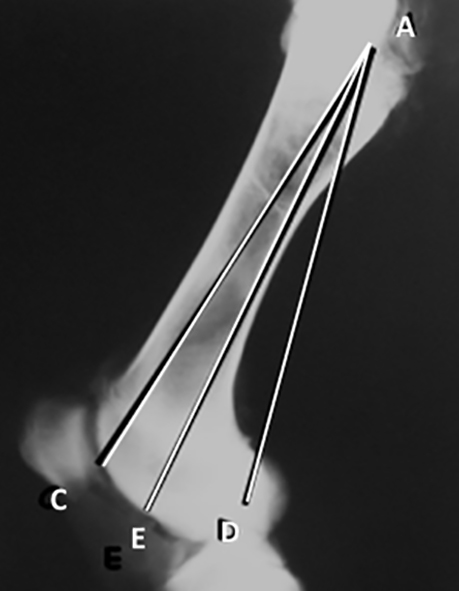

Se realizaron radiografías, antero-posterior y lateral de los fémures y las tibias, postmortem de los miembros inferiores. Las radiografías fueron medidas. En las radiografías antero-posterior del fémur se trazaron y midieron 6 líneas (Figura 1).

Figura 1: Radiografía de fémur antero-posterior. Líneas desde la punta del trocánter mayor. A-D: a la región más lateral del cóndilo lateral. A-E: al intercóndilo. A-C: a la región más medial del cóndilo medial.

(Figura 2): 1. A-D: desde la punta del trocánter mayor a la región más lateral del cóndilo lateral. 2. A-E: desde la punta del trocánter al intercóndilo. 3. A-C: desde la punta del trocánter a la región más medial del cóndilo medial. 4. B-D: desde el centro de la cabeza a la región más lateral del cóndilo. 5. B-E: desde el centro de la cabeza al intercóndilo.  6. B-C: desde el centro de la cabeza a la región más medial del cóndilo medial.

Figura 2:Radiografía de fémur antero-posterior. Líneas desde el centro de la cabeza. B-D: a la región más lateral del cóndilo. B-E: al intercóndilo. B-C: a la región más medial del cóndilo medial.